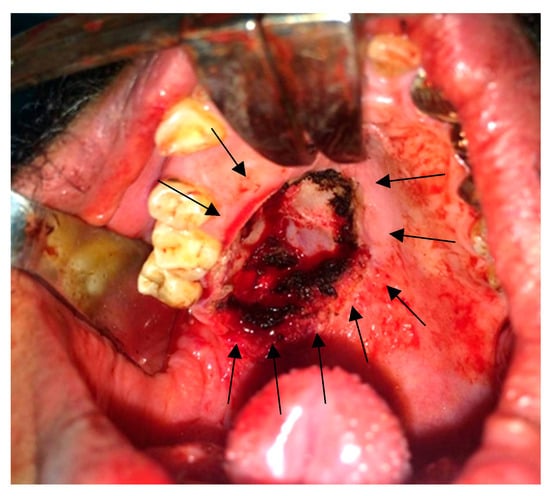

2.5. Surgical Findings